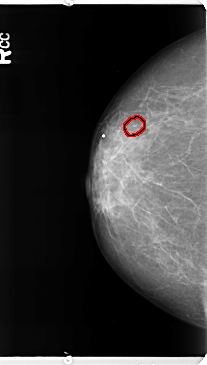

B_3364_1.RIGHT_CC

FILE: B_3364_1.RIGHT_CC.OVERLAY

TOTAL_ABNORMALITIES 1

ABNORMALITY 1

LESION_TYPE CALCIFICATION TYPE PLEOMORPHIC DISTRIBUTION CLUSTERED

ASSESSMENT 4

SUBTLETY 3

PATHOLOGY BENIGN

TOTAL_OUTLINES 1

BOUNDARY